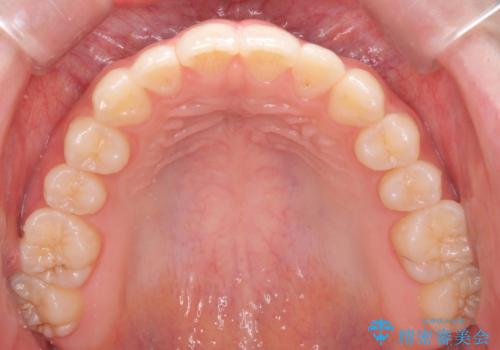

咬んでも向こう側が見える、前歯が閉じない症状でした。また、上の前歯が少し前に出ている状態でした。

上の前歯をわずかに削る処置を行い、後ろに下げながら下の歯となるべく咬むように矯正治療を行いました。